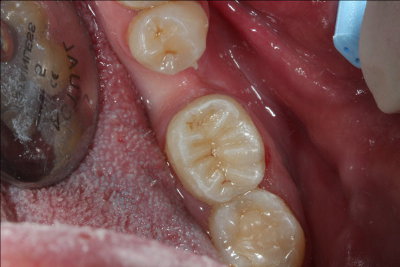

Caso práctico de endodoncia. Clínica Dental Fernández León Caso práctico de endodoncia. Clínica Dental Fernández León